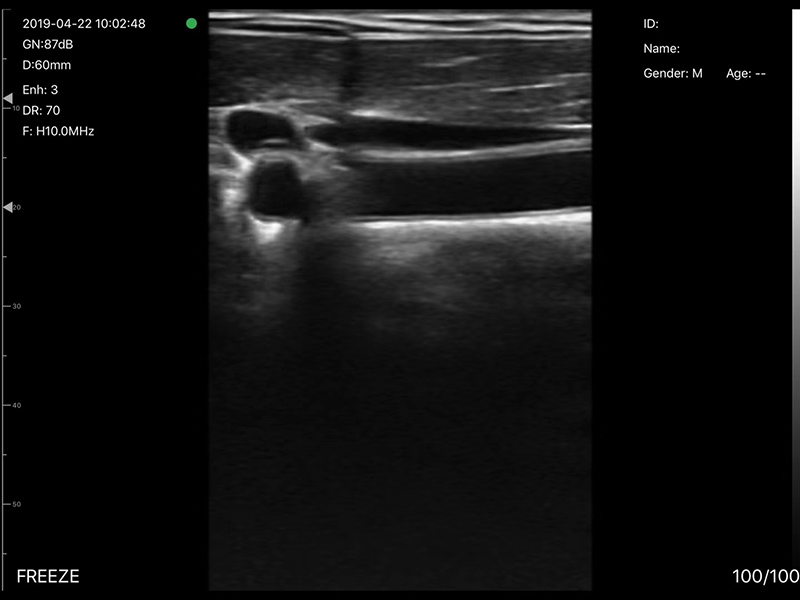

• 探头频率:7.5/10MHz

• 扫描深度:20/40/60/100mm,可调

• 显示模式:B、B/M、CF、PW、PDI

• 穿刺辅助功能:平面内穿刺引导线功能,

平面外穿刺引导与血管自动测量功能,针尖显影增强功能